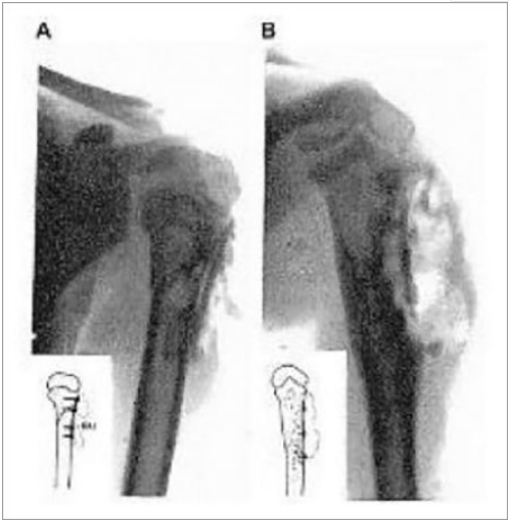

A, B为采用镁板和镁钉为儿童的踝部骨折进行固定

A术后X光显示有气泡形成;B镁板术后3周已基本腐蚀降解